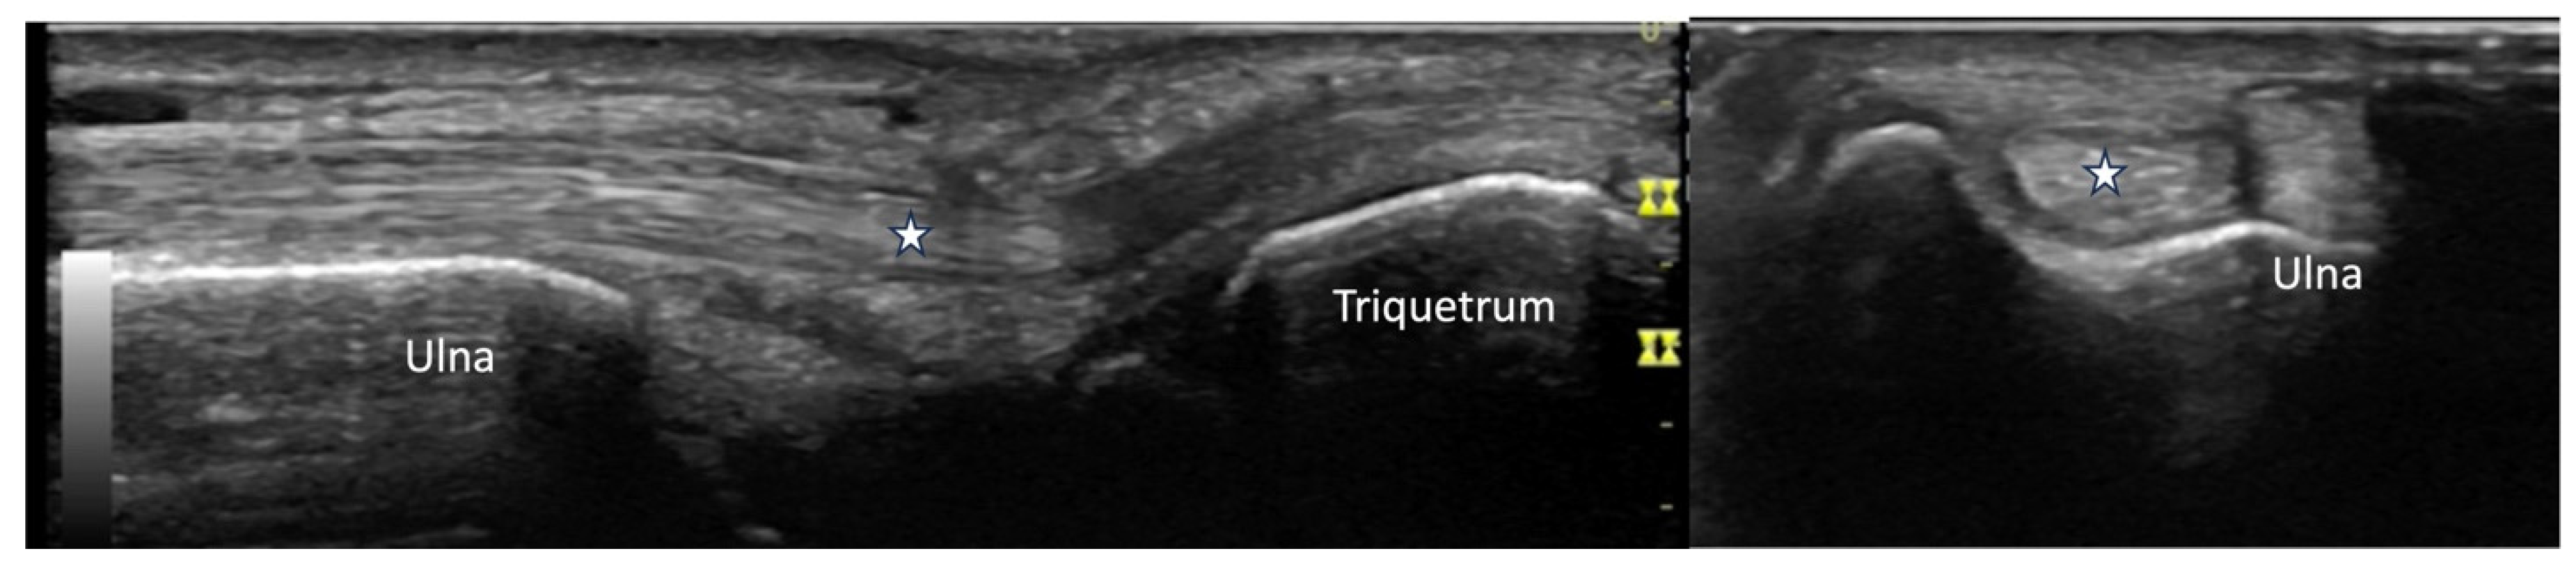

4.2.3. Ulnar Aspect

4.2.4. Radial Aspect